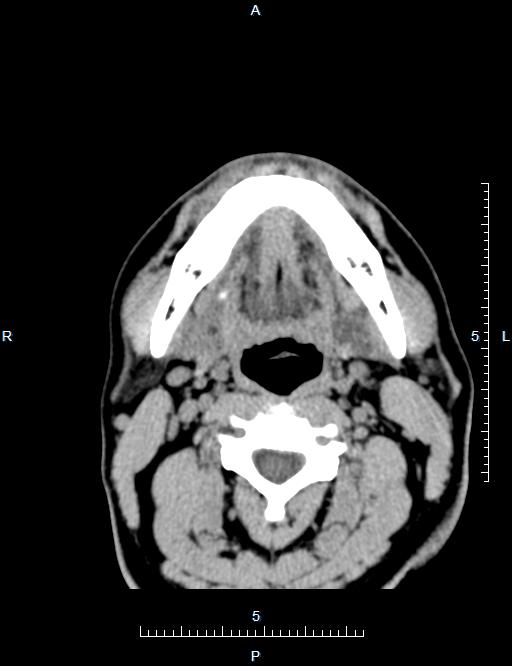

CT49883:颌下腺CT

男,41岁,右侧颌下腺肿大1个月。

考虑 颌下腺腺瘤

炎性

右腮腺多形性腺瘤或混合瘤

右侧颌下腺炎性肿大?

颌下腺炎性病变可能性大

颌下腺腺瘤伴结石可能